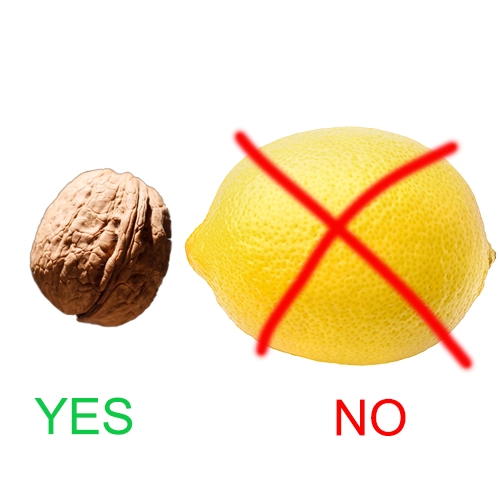

Prostate Size Reduction:

Your prostate should be more the size of a walnut, not a lemon...

...Prosta-7 contains nutrients that help shrink the prostate in men with enlarged prostates...

...Contains phytosterol, which is a protective compound that may be responsible for reducing prostate enlargement.